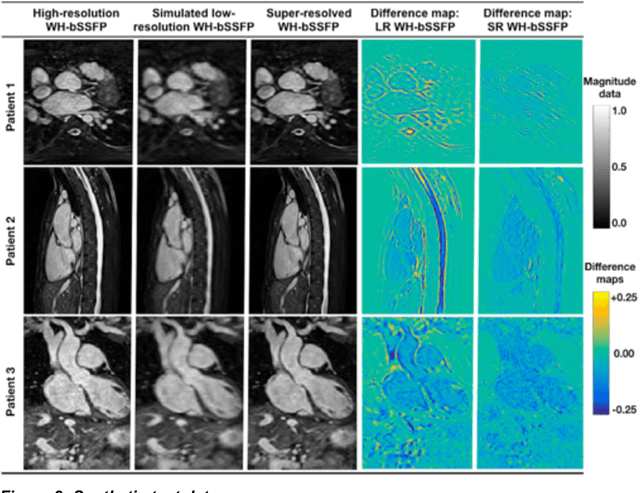

Background: Three-dimensional, whole heart, balanced steady state free precession (WH-bSSFP) sequences provide delineation of intra-cardiac and vascular anatomy. However, they have long acquisition times. Here, we propose significant speed ups using a deep learning single volume super resolution reconstruction, to recover high resolution features from rapidly acquired low resolution WH-bSSFP images. Methods: A 3D residual U-Net was trained using synthetic data, created from a library of high-resolution WH-bSSFP images by simulating 0.5 slice resolution and 0.5 phase resolution. The trained network was validated with synthetic test data, as well as prospective low-resolution data. Results: Synthetic low-resolution data had significantly better image quality after super-resolution reconstruction. Qualitative image scores showed super-resolved images had better edge sharpness, fewer residual artefacts and less image distortion than low-resolution images, with similar scores to high-resolution data. Quantitative image scores showed super-resolved images had significantly better edge sharpness than low-resolution or high-resolution images, with significantly better signal-to-noise ratio than high-resolution data. Vessel diameters measurements showed over-estimation in the low-resolution measurements, compared to the high-resolution data. No significant differences and no bias was found in the super-resolution measurements. Conclusion: This paper demonstrates the potential of using a residual U-Net for super-resolution reconstruction of rapidly acquired low-resolution whole heart bSSFP data within a clinical setting. The resulting network can be applied very quickly, making these techniques particularly appealing within busy clinical workflow. Thus, we believe that this technique may help speed up whole heart CMR in clinical practice.